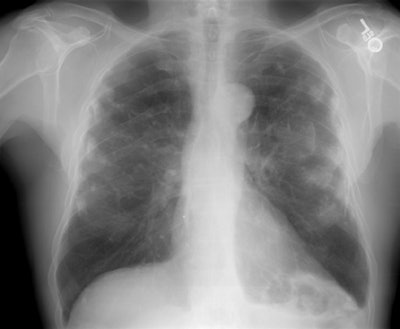

Pleural plaque disease

The case below demonstrates extensive pleural plaque disease in a patient with a history of asbestos exposure: